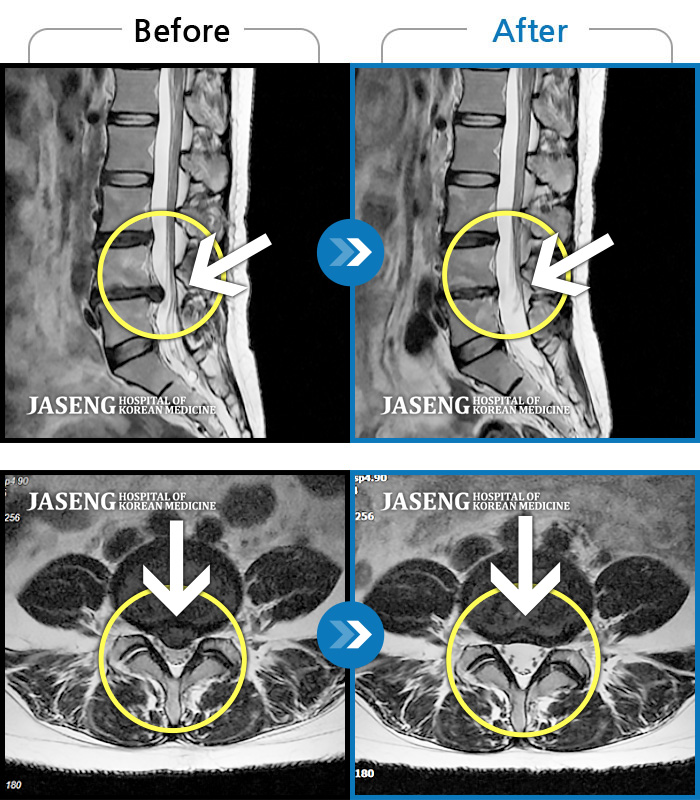

MRI 치료사례

허리디스크로 인한 골반 통증